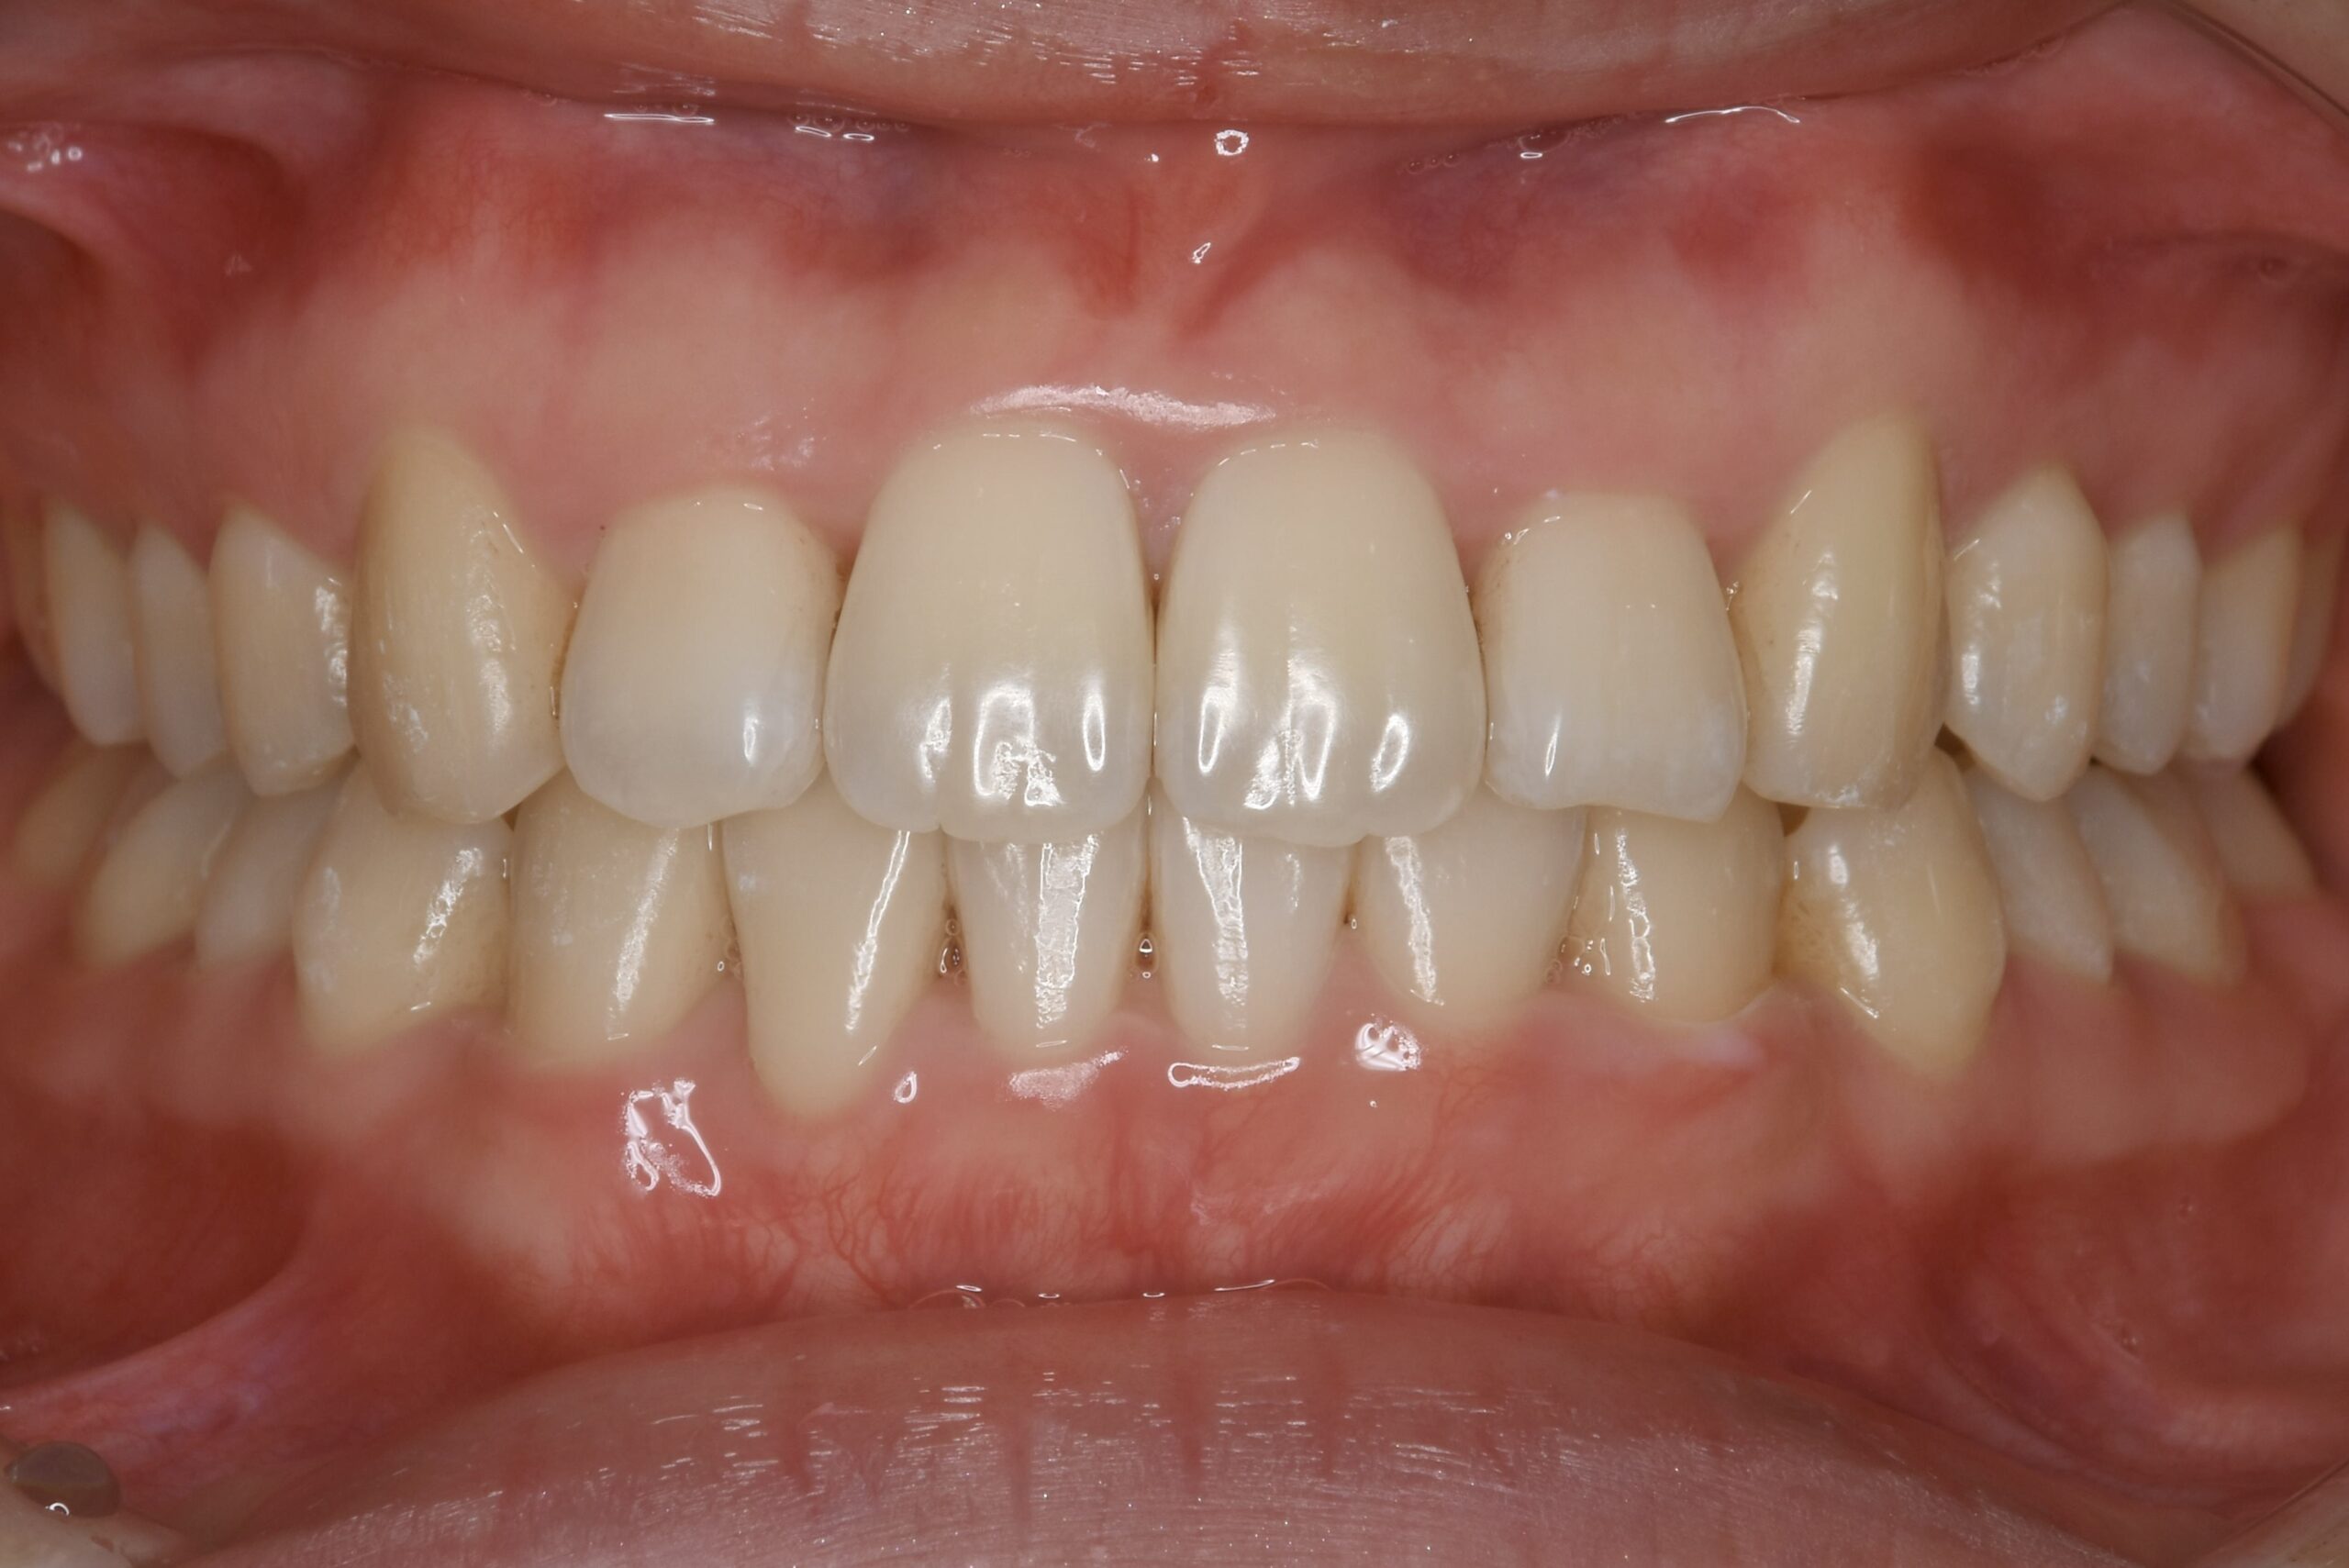

永久歯が生え揃ってから行う矯正歯科治療です。

患者様それぞれのご希望を叶えられるよう、難症例にも対応できる装置はもちろん、治療中の見た目を気にされている方も安心できる、透明で目立たないマウスピース型矯正装置もご用意しております。